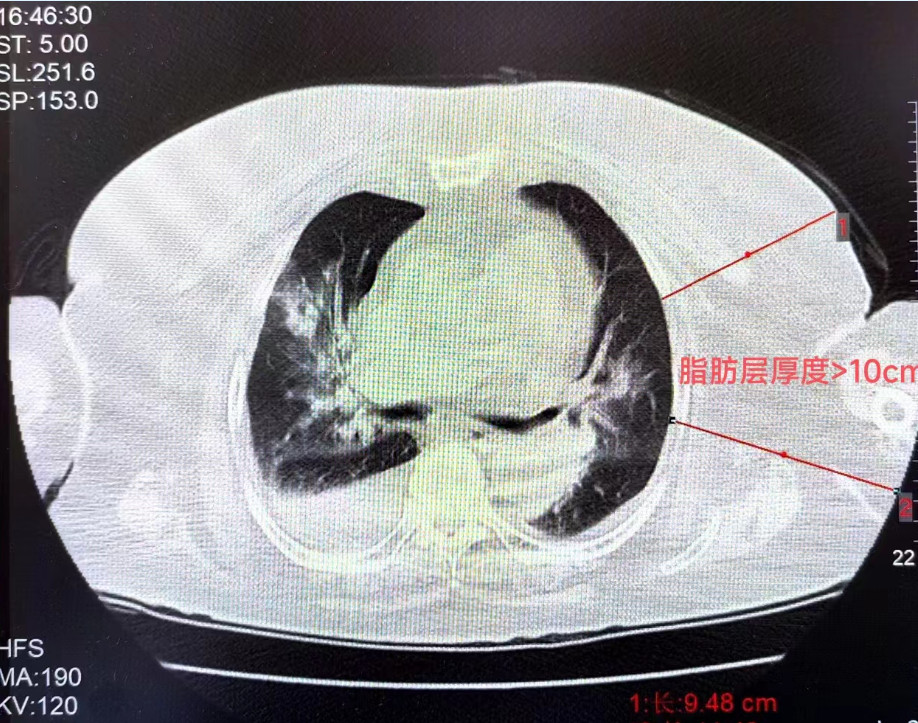

王女士(化名)身高156.5cm,體重90kg,BMI(體重指數(shù))36.7kg/㎡(BMI正常范圍是18.5~23.9),腰圍116cm,臀圍121cm,一晚上睡眠395分鐘中,呼吸暫停了427次,單次最長憋氣時間74秒,AHI指數(shù)(呼吸暫停、低通氣指數(shù))高達71.8。

福建省人民醫(yī)院呼吸科副主任醫(yī)師林勁榕表示,這是2月初醫(yī)院心內(nèi)科請他會診的病人。林勁榕剛見到王女士時,她清醒時的二氧化碳最高達到116mmHg,屬于極重度二氧化碳潴留,正常值應在35-45mmHg,患者最低血氧48%,提示極重度低血氧,合并嚴重心肺功能不全。

通過睡眠監(jiān)測、肺功能等檢查,結合病情等,醫(yī)生們得出結論——原來,缺氧和超高二氧化碳分壓竟是肥胖惹的禍——王女士確診為肥胖低通氣綜合征。